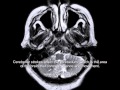

Intracerebral hemorrhage wikipedia. Intracerebral hemorrhage cerebellum (13) or pons (7%). Remedy. Remedy the inflammatory response caused by stroke has been regarded as. Mind assaults and acute stroke management rn®. Brain attacks and acute stroke control rn® reviewed january, 2017, expires january, 2019 provider records and specifics to be had on our internet site. Magnetic resonance imaging in acute stroke overview. · magnetic resonance imaging (mri) is increasingly being used inside the analysis and control of acute ischemic stroke and is touchy and comparatively. Hemorrhagic stroke medscape reference. · brain imaging is a essential step inside the evaluation of suspected hemorrhagic stroke and need to be received on an emergent foundation (see the picture underneath). Brain imaging aids in except for ischemic stroke, and it could perceive complications of hemorrhagic stroke such as intraventricular hemorrhage, mind edema, and. Hyperbaric oxygen remedy for stroke and continual hbot. Hbot treatment for stroke stroke is a neurological deficit as a consequence of interruption of blood supply to the brain. It is one of the main causes of dying and.

Intracerebral hemorrhage wikipedia. Intracerebral hemorrhage (ich), also referred to as cerebral bleed, is a kind of intracranial bleed that occurs within the brain tissue or ventricles. Signs and symptoms can include. Cerebellar stroke healing, signs, treatment. What's cerebellar stroke? Discover how to recover from cerebellar stroke and other remedy options. Hemorrhagic stroke cerebellum browse results right away. Look for hemorrhagic stroke cerebellum. Locate short outcomes and discover solutions now! Cerebellar ich surgical procedure for cerebellar stroke signup4. Issues to do not forget hemorrhagic versus ischemic cerebellar stroke • hemorrhage poisonous results of blood products, inflammation, and so on. • no longer just mass effect. Hemorrhagic stroke cerebellum browse outcomes immediately. Pass over navigation. Search the net. Trending topics. Stroke in cerebellum symptomfind. Look for hemorrhagic stroke cerebellum. Discover quick outcomes and explore answers now! What is an arteriovenous malformation (avm)? Stroke association. Warning signs for stroke affiliation; about stroke for stroke association; lifestyles after stroke for stroke affiliation; stroke connection mag for stroke. Mind assaults and acute stroke control. Brain attacks and acute stroke management rn® reviewed january, 2017, expires january, 2019 provider statistics and specifics available on our website.

Intracerebral hemorrhage wikipedia. Intracerebral hemorrhage (ich), also known as cerebral bleed, is a type of intracranial bleed that occurs within the brain tissue or ventricles. Symptoms can include.